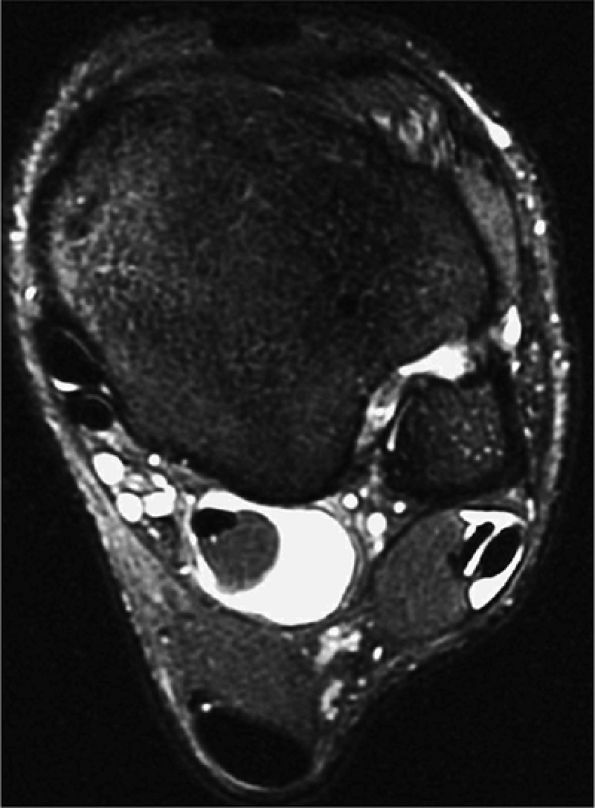

FIGURE 5.9 ● FLEXOR HALLUCIS LONGUS The flexor hallucis longus (FHL) flexes the great toe and plantarflexes the foot. The FHL is susceptible to injury during extremes of ankle plantarflexion and metatarsophalangeal dorsiflexion. The proximal sheath, 10 to 12 cm in length, has no mesotenon and may communicate with both the ankle joint and the sheaths of the flexor digitorum longus and tibialis posterior.